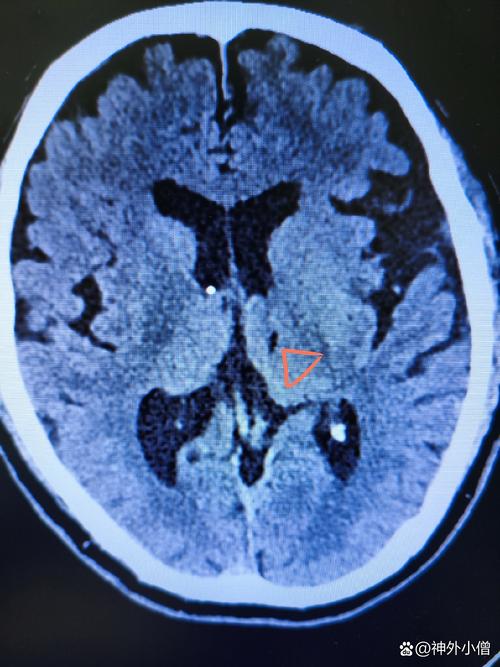

(图片来源网络,侵删)

关键在于区分“脑梗”本身和“脑梗的后果/原因”,陈旧性脑梗指的是发病时间超过数周甚至数月的脑梗死病灶,这个病灶本身(已经坏死的脑组织)是无法通过手术“复活”的,围绕陈旧性脑梗,有两类主要的手术情况: